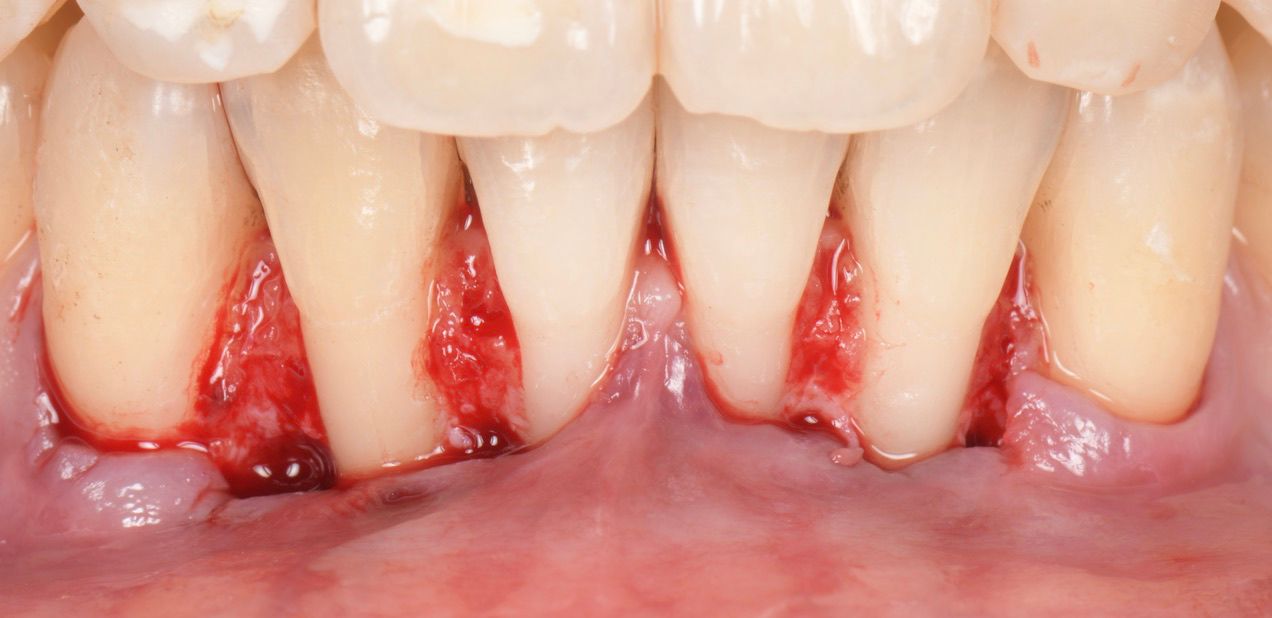

A 35-year-old female, healthy (ASA I), non-smoker, with no medication, came to our practice complaining about gingival recession and pain while brushing her mandibular incisors.

The intraoral examination revealed multiple RT 1 (Cairo 2011) gingival recessions on teeth #33 to #43, along with a thin tissue phenotype, which was associated with a traumatic toothbrushing habit (Fig. 1).

Two split-full-split flaps were raised from teeth #33 to #31 and #41 to #43, with beveled incisions at the base of the papilla (Fig. 3).

De-epithelialization of the anatomical papilla (Fig. 4).

Root planing and surface conditioning with Straumann® Prefgel® for 2 minutes (Fig. 5).